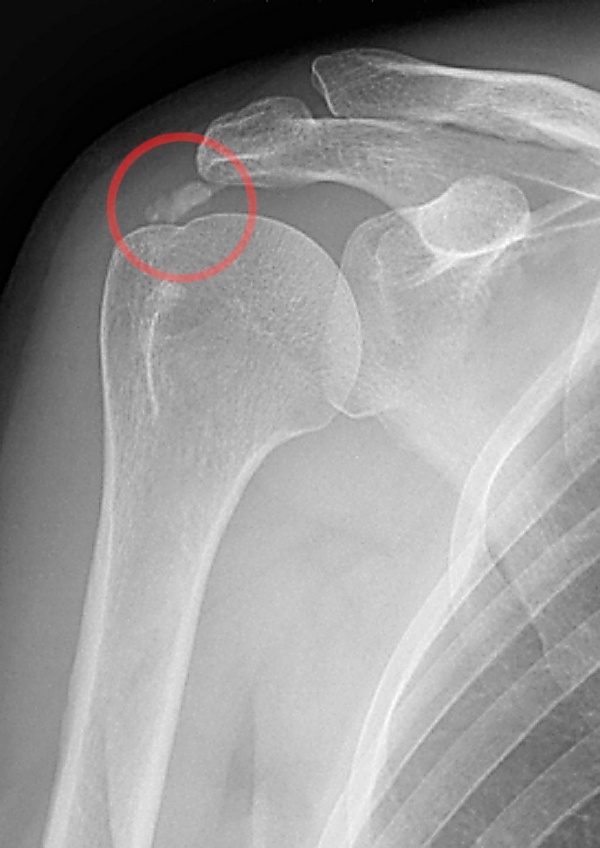

Кальцифицирующий тендинит

Кальцифицирующий тендинит — отложение гидроксиапатита в сухожилии, проявляющееся болью и ограничением подвижности в суставе[2][3]. Встречается чаще у женщин в возрасте 30—50 лет[4]. Причины неизвестны. В лечении используют физиотерапию, лечебную физкультуру, противовоспалительные препараты и удаление кальцинатов[5].

- рентгенография сустава (помогает визуализировать кальцификаты);